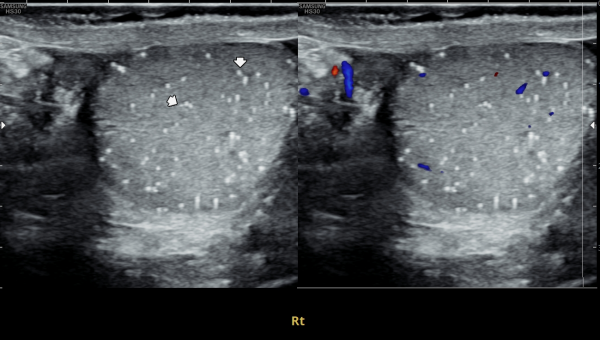

내원 당일 전립선과 사정관 입구와 사정관 그리고 정낭 그리고 정관등의 표적 치료후 치료된 현미경학적 자료 입니다.

This is a microscopic image taken after the targeted treatment of the prostate, ejaculatory duct openings, ejaculatory ducts, seminal vesicles, and vas deferens.

주 2회 전립선과 사정관과 사정관 입구 그리고 정낭과 정낭의 표적 치료후 치료된 현미경학적 자료입니다.

This is a microscopic image obtained after twice-weekly targeted treatment of the prostate, ejaculatory ducts and their openings, seminal vesicles, and vas deferens.

The image shows evidence of treatment effect, including shedding of aged or degenerated epithelial cells that were previously blocking the ducts. These cells are associated with inflammation caused by seminal vesicle contents and prostaglandins.

The findings indicate that the treatment helped to clear obstructed and inflamed areas, improving drainage and reducing the blockage that was contributing to symptoms.

주 2회 전립선과 전립선관, 사정관 입구와 사정관과 정낭 그리고 정관등의 표적 치료후 치료된 현미경학적 자료입니다.

This is a microscopic image taken after twice-weekly targeted treatment of the prostate, prostatic ducts, ejaculatory ducts, seminal vesicles, and vas deferens.

It shows tissue fragments and inflammatory materials that had blocked these passages. Through treatment, these obstructive materials were cleared, helping to improve circulation and function.

This process may support better semen flow and reduce symptoms related to blockage or inflammation.

This microscopic image shows material that was cleared after targeted treatment of the prostate, seminal vesicle, ejaculatory duct, and vas deferens.

The substances include:

- Shed epithelial cells (cells that naturally peeled off the lining)

- Protein-like material and fibrin from past inflammation

- Small inflammatory cells

- Trapped sperm fragments

- Tiny micro-stones (micro-calculi)

These are common findings in conditions such as chronic prostatitis, seminal vesiculitis, or ejaculatory duct inflammation. The treatment helps to remove these blockages and inflammatory materials, allowing for healthier circulation and improved function.